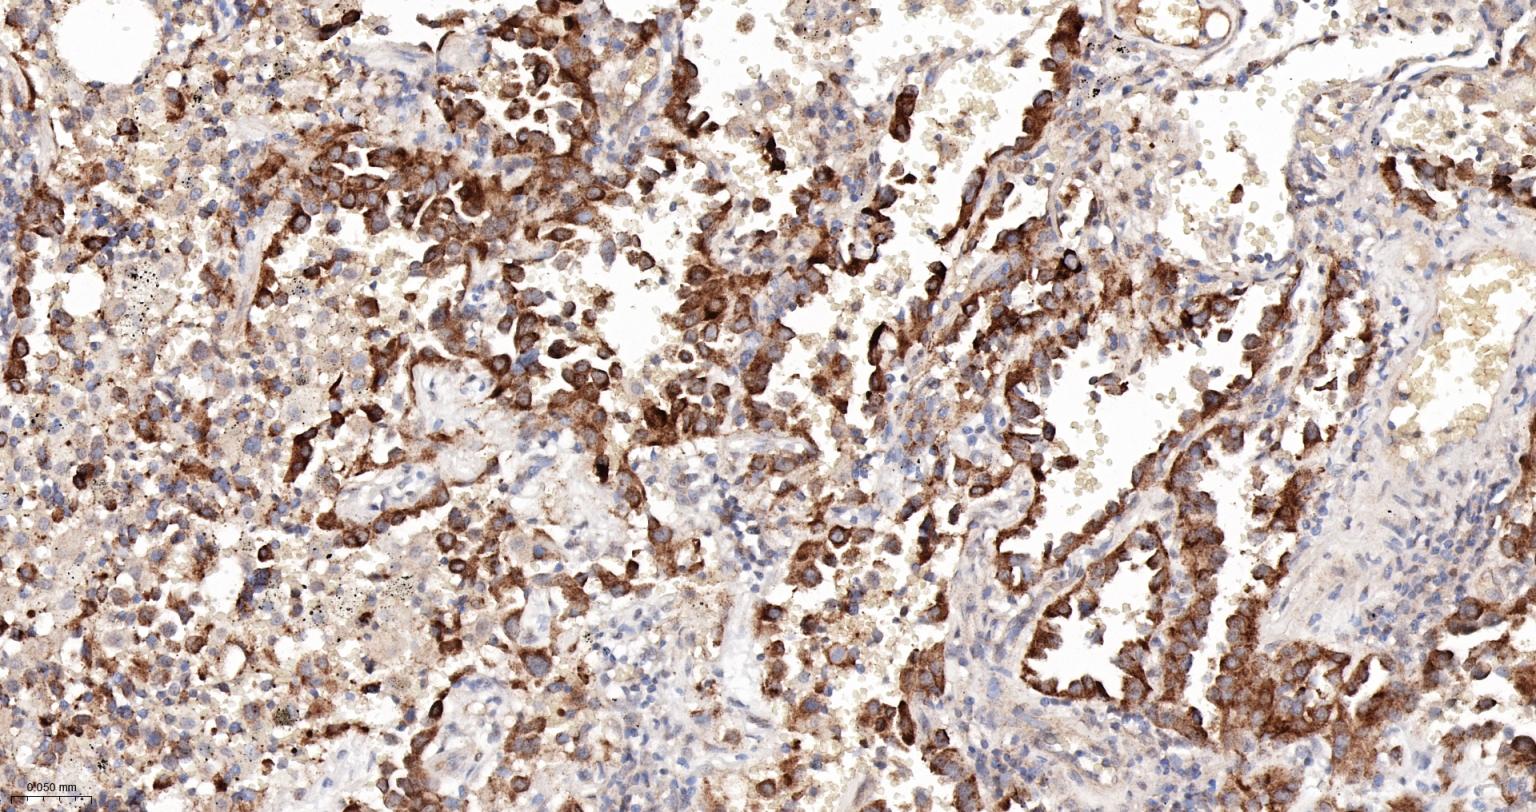

Paraformaldehyde-fixed, paraffin embedded Human Lung Cancer; Antigen retrieval by boiling in sodium citrate buffer (pH6.0) for 15 min; The section was incubated with SOS 1 Monoclonal Antibody, Unconjugated (bsm-61473R) at 1:200 overnight at 4°C, followed by conjugation to the bs-0295G-HRP and DAB (C-0010) staining.